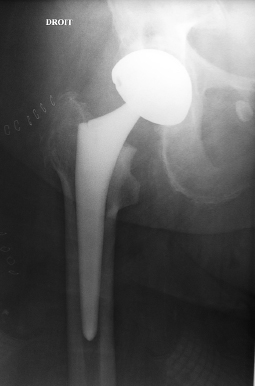

Mme P. née en 1929 a été opérée sans problème d’une prothèse de hanche droite pour coxarthrose. Les radiographies postopératoires immédiates sont parfaites.

Deux mois après, elle ressent une douleur de la cuisse au niveau de la queue de la prothèse, elle continue l’appui qui est de plus en plus douloureux.

La radiographie du 13 février montre la fissure diaphysaire (flèche rouge) et un descellement de la prothèse (flèche bleue).